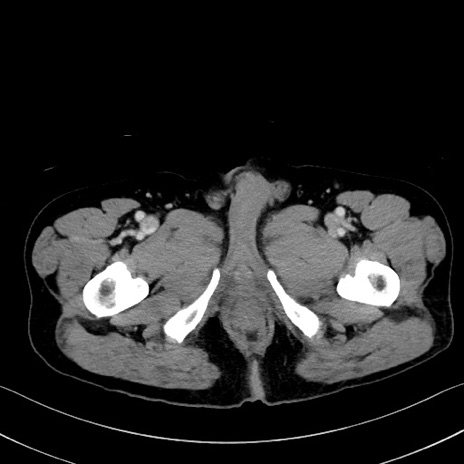

症例35(横断像)

【症例】70歳代 男性

【主訴】腹部膨満、嘔吐

【現病歴】昨日より腹部膨満感出現。本日増悪し、仙痛出現。嘔吐あり、受診。

【既往歴】糖尿病、胆摘後

【身体所見】BP 149/80mmHg、HR 74/min、BT 35.9℃、腹部:膨満、軟、圧痛なし。腸雑音減弱あり。上腹部正中切開瘢痕あり。

【データ】WBC 13500、CRP 1.72